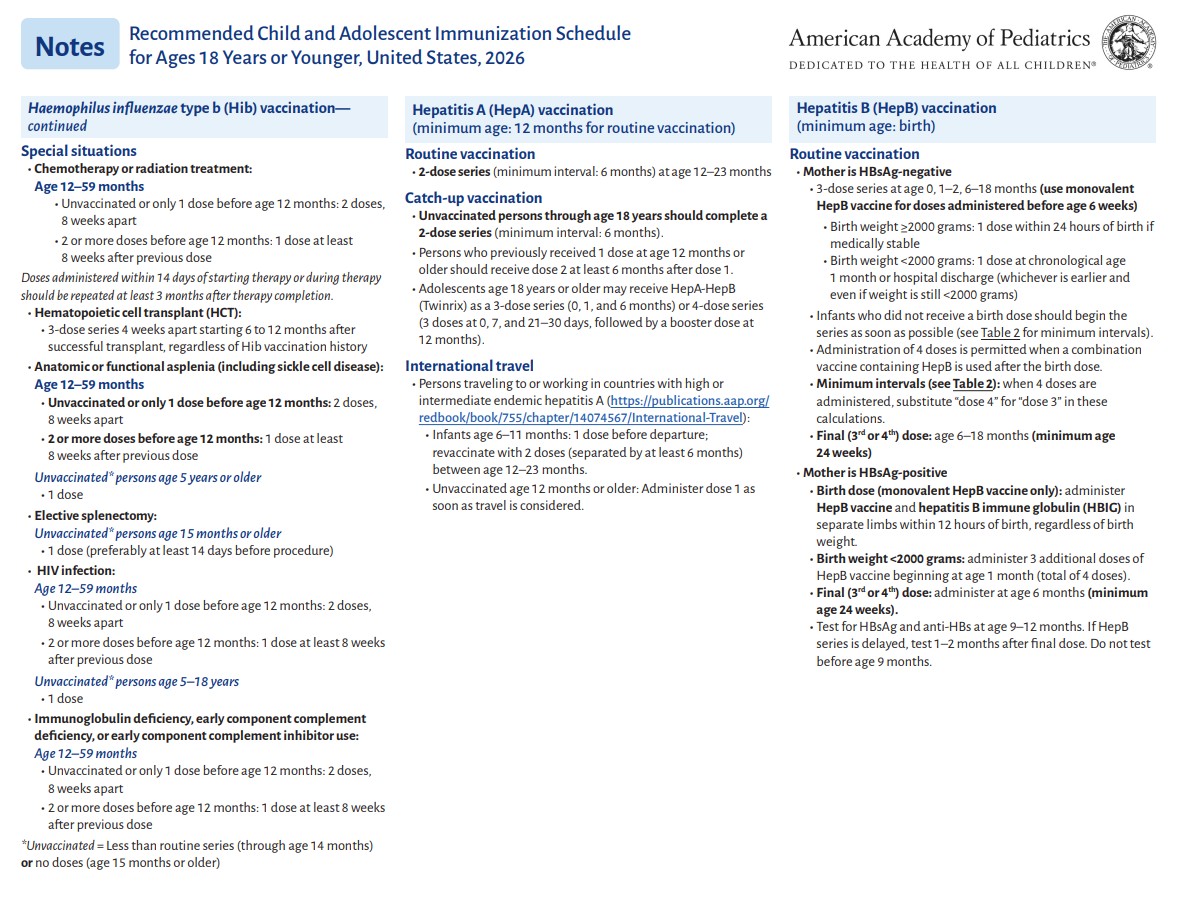

p 4